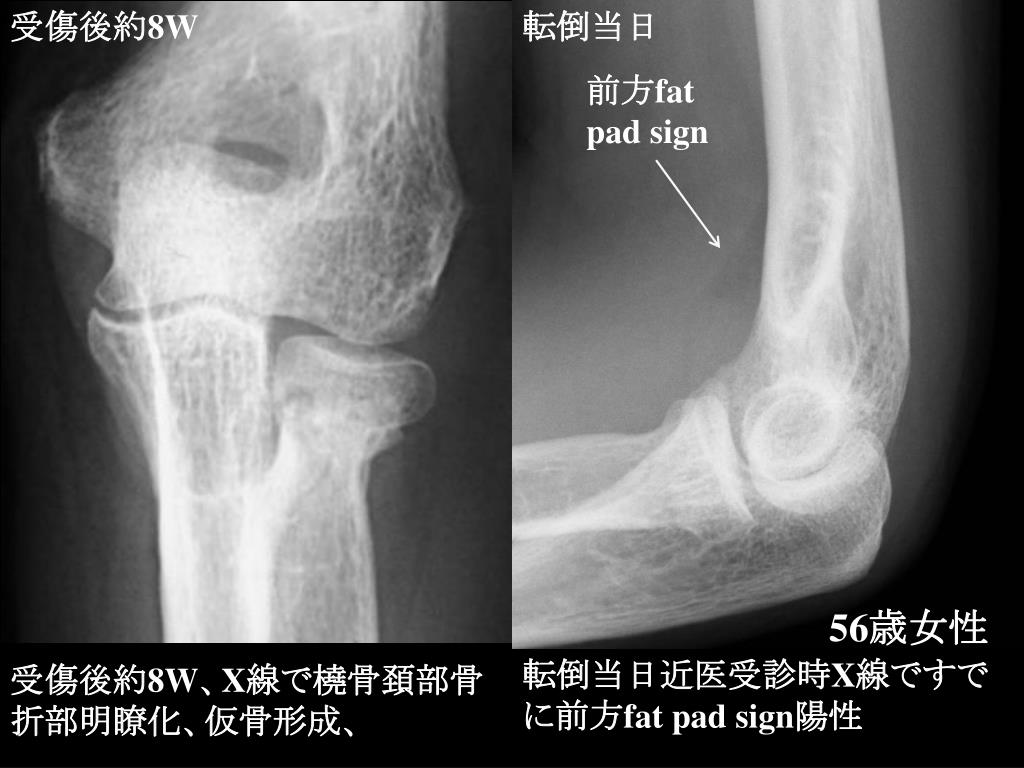

8. 受傷後約8W 転倒当日 前方fat pad sign 56歳女性 転倒当日近医受診時X線ですでに前方fat pad sign陽性 受傷後約8W、X線で橈骨頚部骨折部明瞭化、仮骨形成、